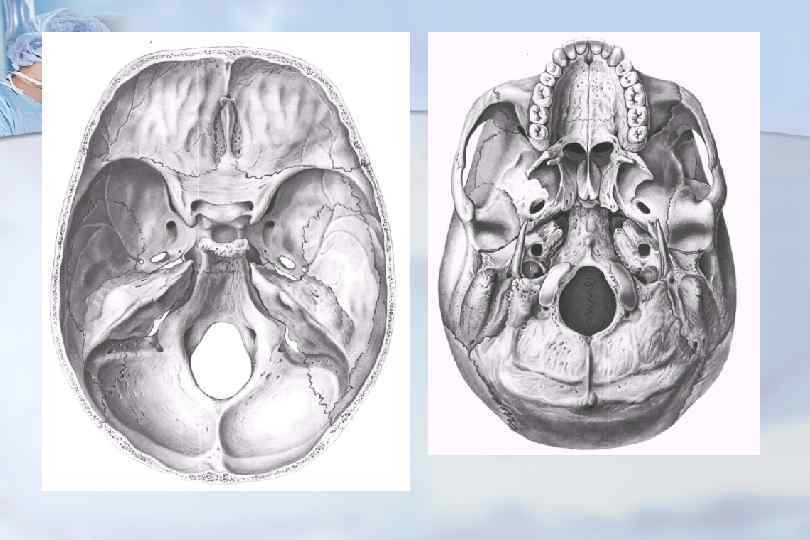

Анатомические детали: Фотографии топографии черепа с нижнего вида

Раздел: Альбом идей